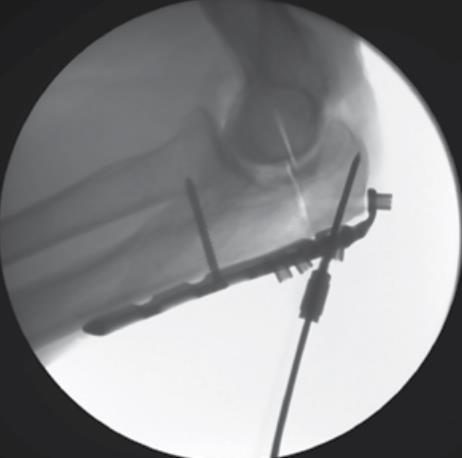

• Provisional K-wire Fixation

• if provisional plate fixation is needed, insert a 2.0mm AIMing Guide into the desired PDG, then drive a 2.0mm k-wire through the AIMing Guide, taking care to avoid the articular surfaces of the joint

• using the 2.7mm drill bit, drill through the PDG

• if a K-Wires obstructs drilling, it may be bent out of the way

• Preparing the Home Run Tab

• confirm that the HR tab is flush to the tip of the olecranon

• using the 2.7mm x 80mm drill bit, drill through the PDG, then measure and record the screw length using the appropriate scale on the 80mm Depth Gauge

• note: if the HR tab was bent, confirm that the new trajectory will avoid contact with the articular surfaces of the joint

• Over Drilling the Home Run Tab

• using the T-10 Driver, remove the PDG in the HR tab

• drill up to the fracture line using the 3.5mm drill bit

• fluoroscopic imaging is helpful during this step